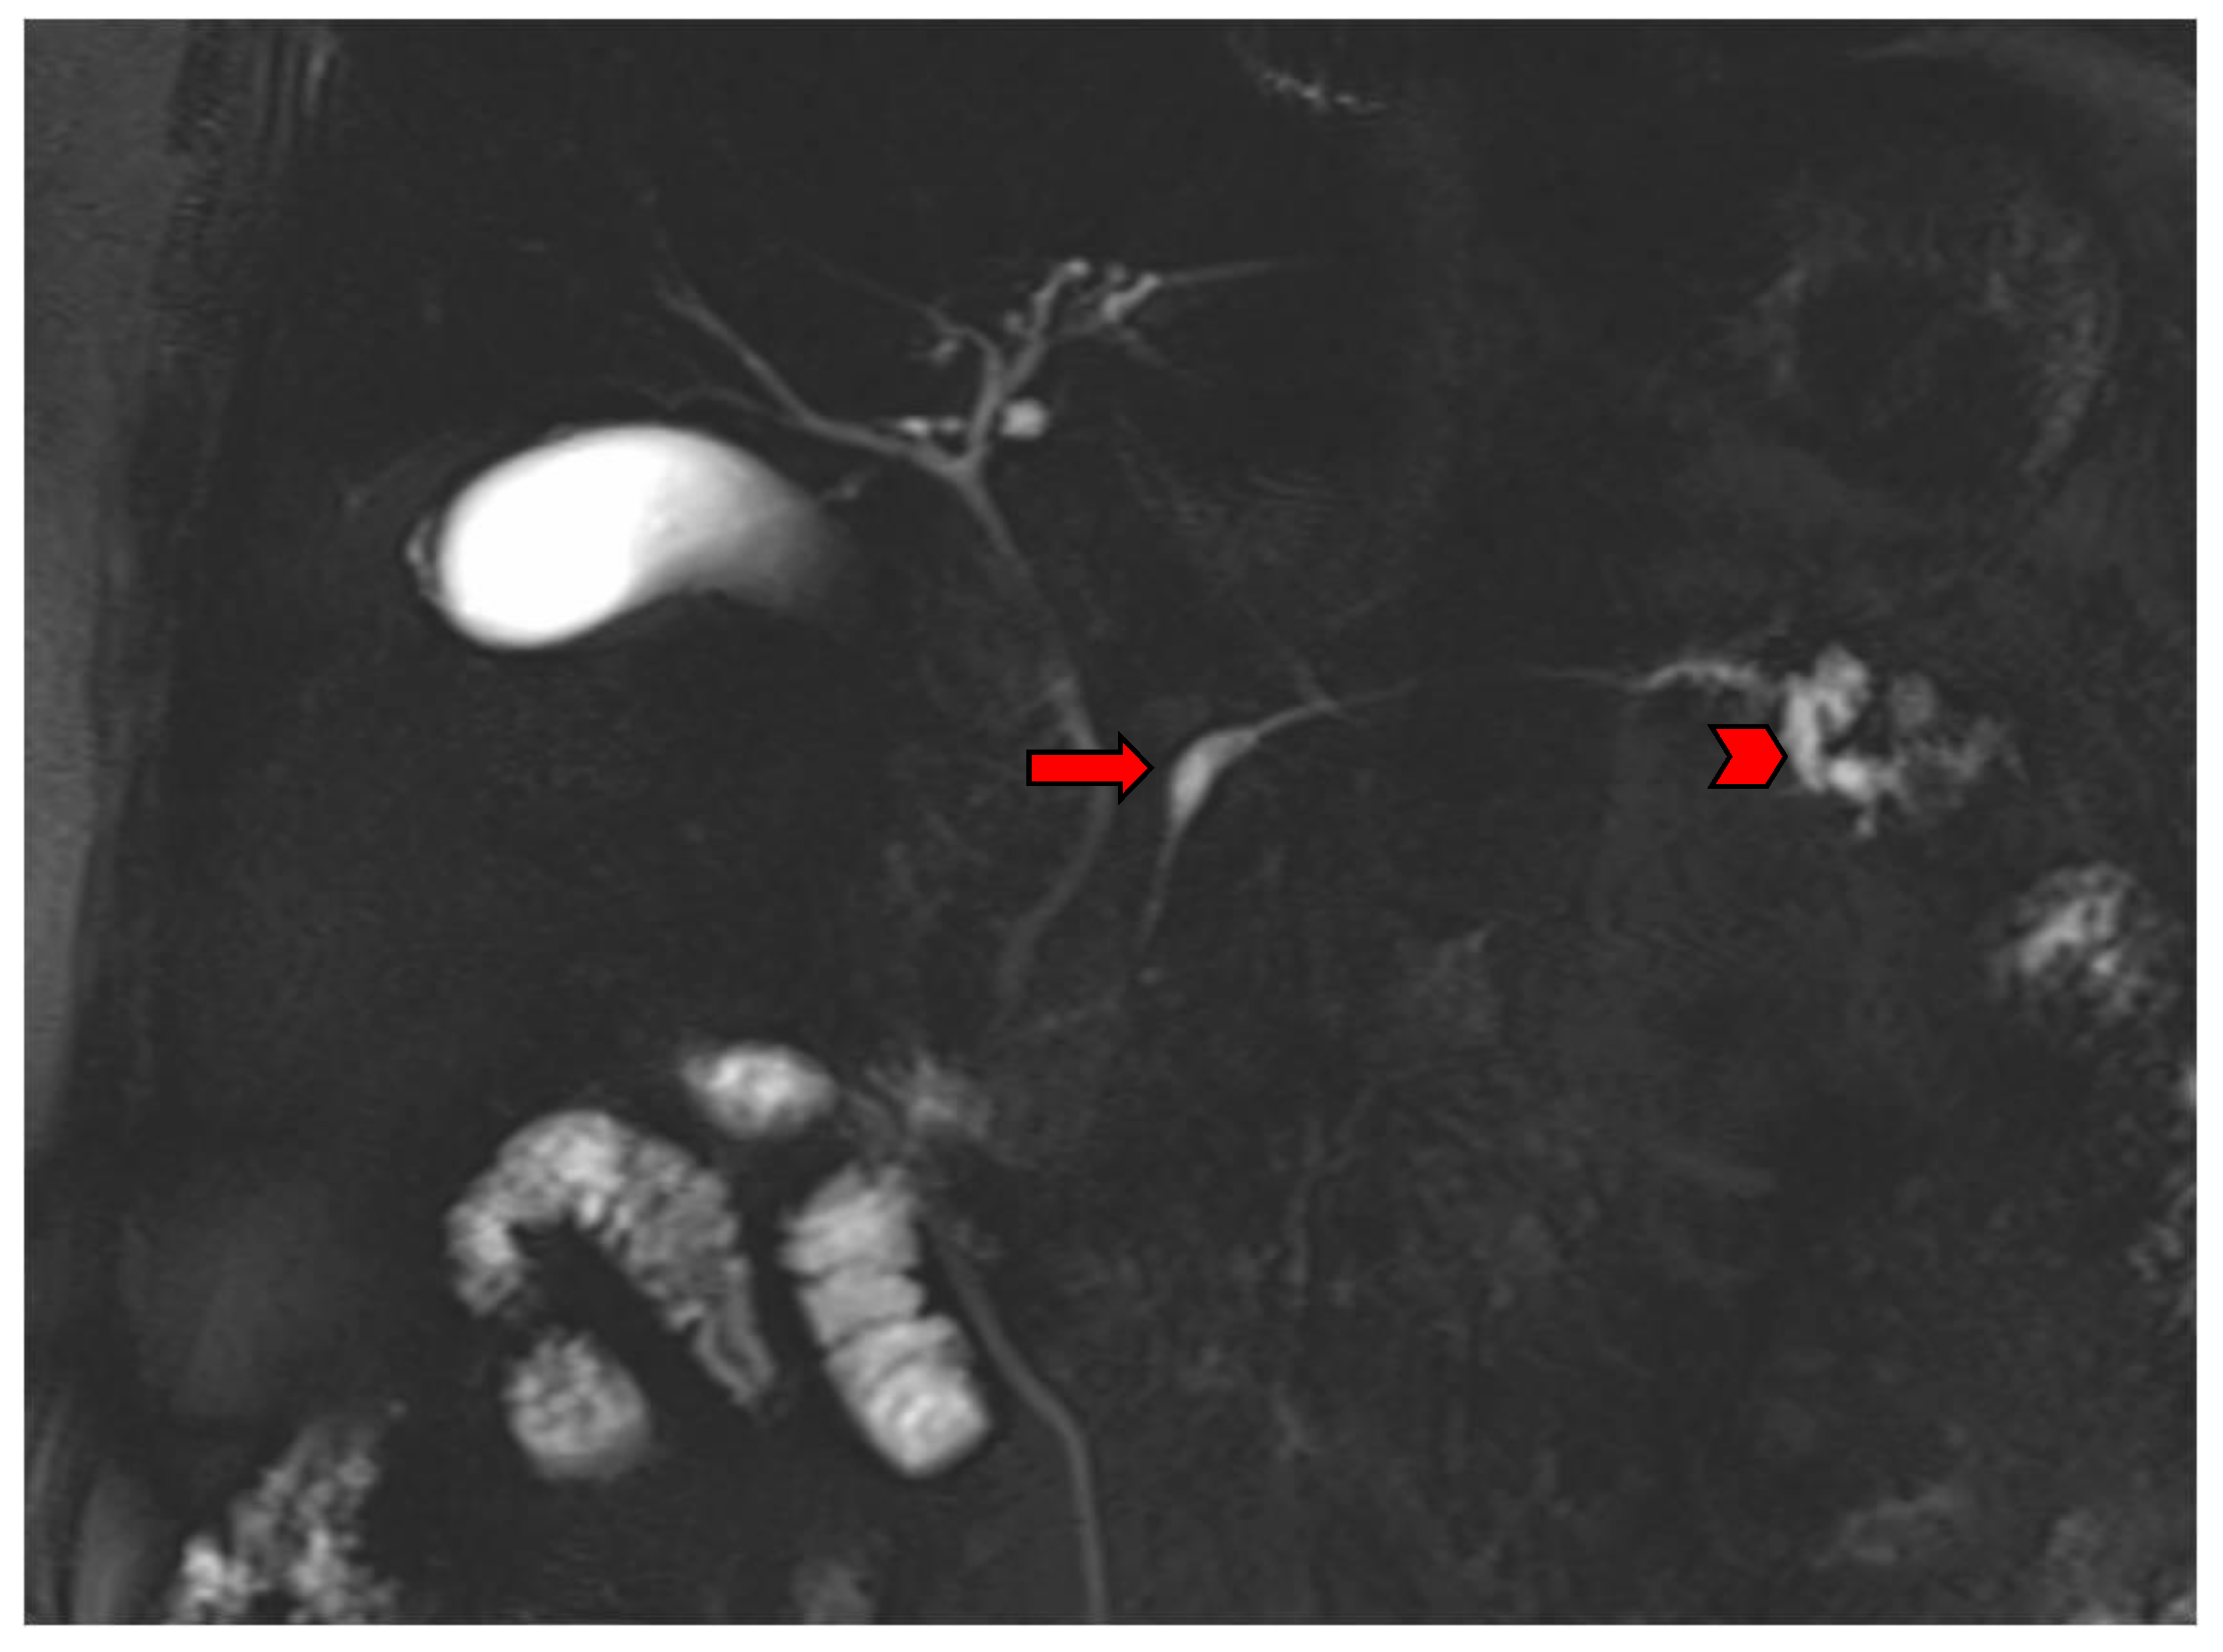

2. Imaging Findings